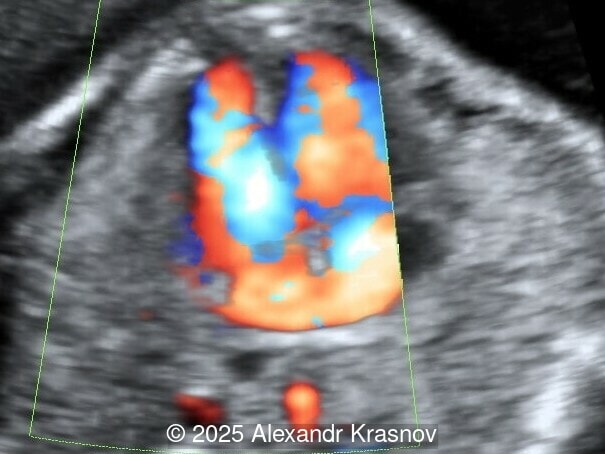

Our ultrasound showed biometry data corresponding to 21 weeks of gestation. During echocardiography, an abnormal drainage of the pulmonary veins was detected in which the pulmonary veins drain into a venous collector linked to the superior vena cava. The four-chamber view and the three-vessel view were altered and raised suspicion of a pathology. The grayscale and color Doppler images of the four-chamber view indicate a smooth posterior wall of the left atrium, increased distance between the left atrium and the descending aorta and the absence of pulmonary veins entering the left atrium (Image 1, 2; Video 1, 2). In the three-vessel view, the diameter of the superior vena cava appears larger than that of the aorta (Image 3, Video 3). In the images of the venae cava, a significant difference is seen between the diameters of the inferior and superior vena cava with significant enlargement of the superior vena cava (Image 4, Video 4). Additionally, there is a pulmonary venous confluent chamber (“twig sign”) behind the left atrium (Image and Video 5). A vertical ascending vein connects the confluent chamber with the superior vena cava where it drains blood from the pulmonary veins (Images 6, 7; Video 6).

Direct markers are based on anatomical features in TAPVR, and their presence usually confirms the diagnosis. Some appear in all types of TAPVR, and others are specific to particular types. A lack of connection between the pulmonary veins and the left atrium or the presence of a confluent chamber can be found in all types of TAPVR. Whereas the presence of an ascending or descending vertical vein is found in supracardiac or infracardiac types. Normal entry of a left and right pulmonary vein at the posterior wall of the left atrium (horn‑like insertion) is absent, which leads to a completely smooth posterior wall in the four-chamber view [6,7]. The “twig sign” represents the entry of the pulmonary veins into a confluent chamber behind the left atrium [7], and is visible in the four‑chamber view except in the cardiac type. In the cardiac type, the confluent vein is located more inferiorly, below the plane of the four‑chamber view and does not form a twig sign, making it more difficult to detect [5]. In supracardiac TAPVR, an ascending vertical vein can be observed in the 3-vessel tracheal view as an additional vessel, usually located at the left of the main pulmonary artery. In infracardiac TAPVR, the descending vertical vein can be seen as an additional vein in the axial abdominal plane [8].

In many cases, direct signs are not visualized, thus identification of indirect signs allow us to suspect this pathology, not diagnose it. They are based on morphological findings such as increased post‑left atrium space, or on hemodynamic changes such as ventricular disproportion, dilated superior vena cava or coronary sinus, and abnormal Doppler waveforms. The presence of a pulmonary venous confluence leads to an increased distance between the left atrium (LA) and the descending aorta (DAo) [9]. While visualization of the confluent chamber may be difficult, objectively measuring the increase in the space behind the left atrium in an axial section may be easier to verify. Various indices have been proposed for this purpose, the most widely used being the “post‑LA space index” described by Kawazu et al [10]. It is calculated as the ratio of the LA‑DAo distance to the diameter of the DAo, proposing a value ≥1.27 as a potential marker of TAPVR. In clinical practice, a cut-off of 1.0 may be more useful to increase detection rates, although this would be at the expense of more false positives. An alternative marker with a similar diagnostic performance and independent of the gestational age is the “left atrial posterior space to diagonal ratio,” which is calculated by dividing the LA‑DAo distance by the left atrial diameter, with an optimal cut-off ≥0.35 [11]. Asymmetric ventricular chamber dimensions with right heart dominance result from extra‑abnormal flow from the pulmonary veins to the right heart, providing a diagnostic clue for TAPVR [9], but this finding is late and not very specific. In supracardiac TAPVR, anomalous pulmonary venous drainage increases blood flow to the collector, which travels to the right atrium through the dilated innominate vein and superior vena cava, visible in the three-vessel trachea and bicaval views [7,12]. In the subcostal view of pediatric echocardiography, the cardiac type is characterized by the “whale’s tail sign,” where left and right pulmonary veins drain into the dilated coronary sinus. Although it is a technically difficult plane to obtain in fetal echocardiography, it has been described by Karmegaraj in a 25-week-old fetus [13]. Spectral Doppler waveforms are typically normal or biphasic in cardiac type, whereas in supracardiac and infracardiac types, the waveforms can be biphasic, monophasic, or continuous [6,7]. Color and spectral Doppler assessment allows the identification of the fetuses with pulmonary venous pathway obstruction and, therefore, at risk for acute postnatal deterioration with severe respiratory distress and cyanosis [14].